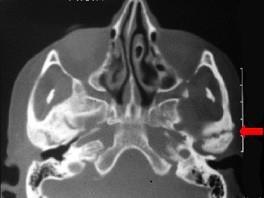

问题 患儿,5岁,外伤后逐渐出现张口困难,咬合关系错乱,髁突动度减弱,外观及X 线检查结果如图。最可能的诊断是 ( )

选项 A.颞下颌关节强直 B.颧骨骨折 C.颧弓骨折 D.下颌骨骨折 E.上颌骨骨折

答案 A